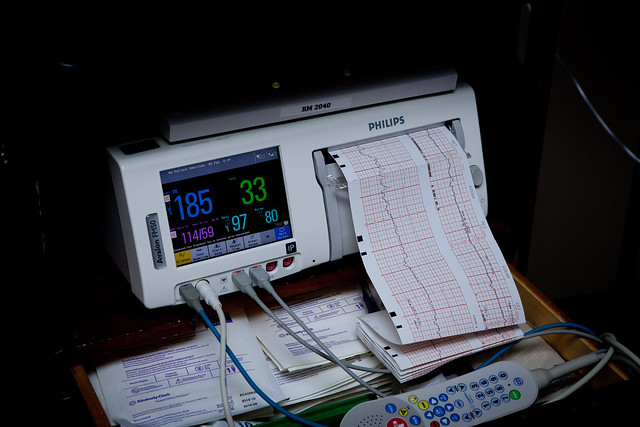

Once we were all set up in the triage room for our hour progression wait, we turned on the Wild game to help pass the time. Again, contractions continued to get stronger throughout that hour and by the end, I needed to stop and breath through them. The only tolerable position for me was to stand and while a contraction would come, I would need to bend over and brace myself on the side of the bed. After our hour wait, I was still dilated to a 4, but was much softer. Thankfully, they decided to admit me even though I hadn’t technically made any progress, but could clearly tell I was in labor and things had intensified since we had come in. It was such a relief to know we were going to have you! I told Daddy if they didn’t admit me, we were just going to go downstairs and hang out in the lobby because there was no way I was leaving. Getting admitted also meant I could get that epidural I was thinking about with every contraction.

Nonetheless, by 11:30 it finally worked and I had some relief. At this point, I had only progressed to a 5. This amazes me. I for sure felt like she was going to check me and i was going to be like a 7. For as often as the contractions were coming and how strong they felt, it seems crazy to think that my body was only half way to where it needed to be to deliver you. By midnight, the nurse suggested getting a little rest. Daddy was pretty tired so he lied down for a little. I sent my work an email to let them know I was in labor, made some notes about labor thus far and closed my eyes to get what little rest I could.

Around 1:30 I started feeling a lot of pressure that was boarder-line uncomfortable/painful. I was thinking that the medication for the epidural was running out. I paged the nurse to let her know. She checked me quick and said I was a 7 with a bulging bag of waters. Either my water was going to break pretty quickly or the Dr. would break it when she arrived, which should be in about 30 minutes.

Around 1:30 I started feeling a lot of pressure that was boarder-line uncomfortable/painful. I was thinking that the medication for the epidural was running out. I paged the nurse to let her know. She checked me quick and said I was a 7 with a bulging bag of waters. Either my water was going to break pretty quickly or the Dr. would break it when she arrived, which should be in about 30 minutes.